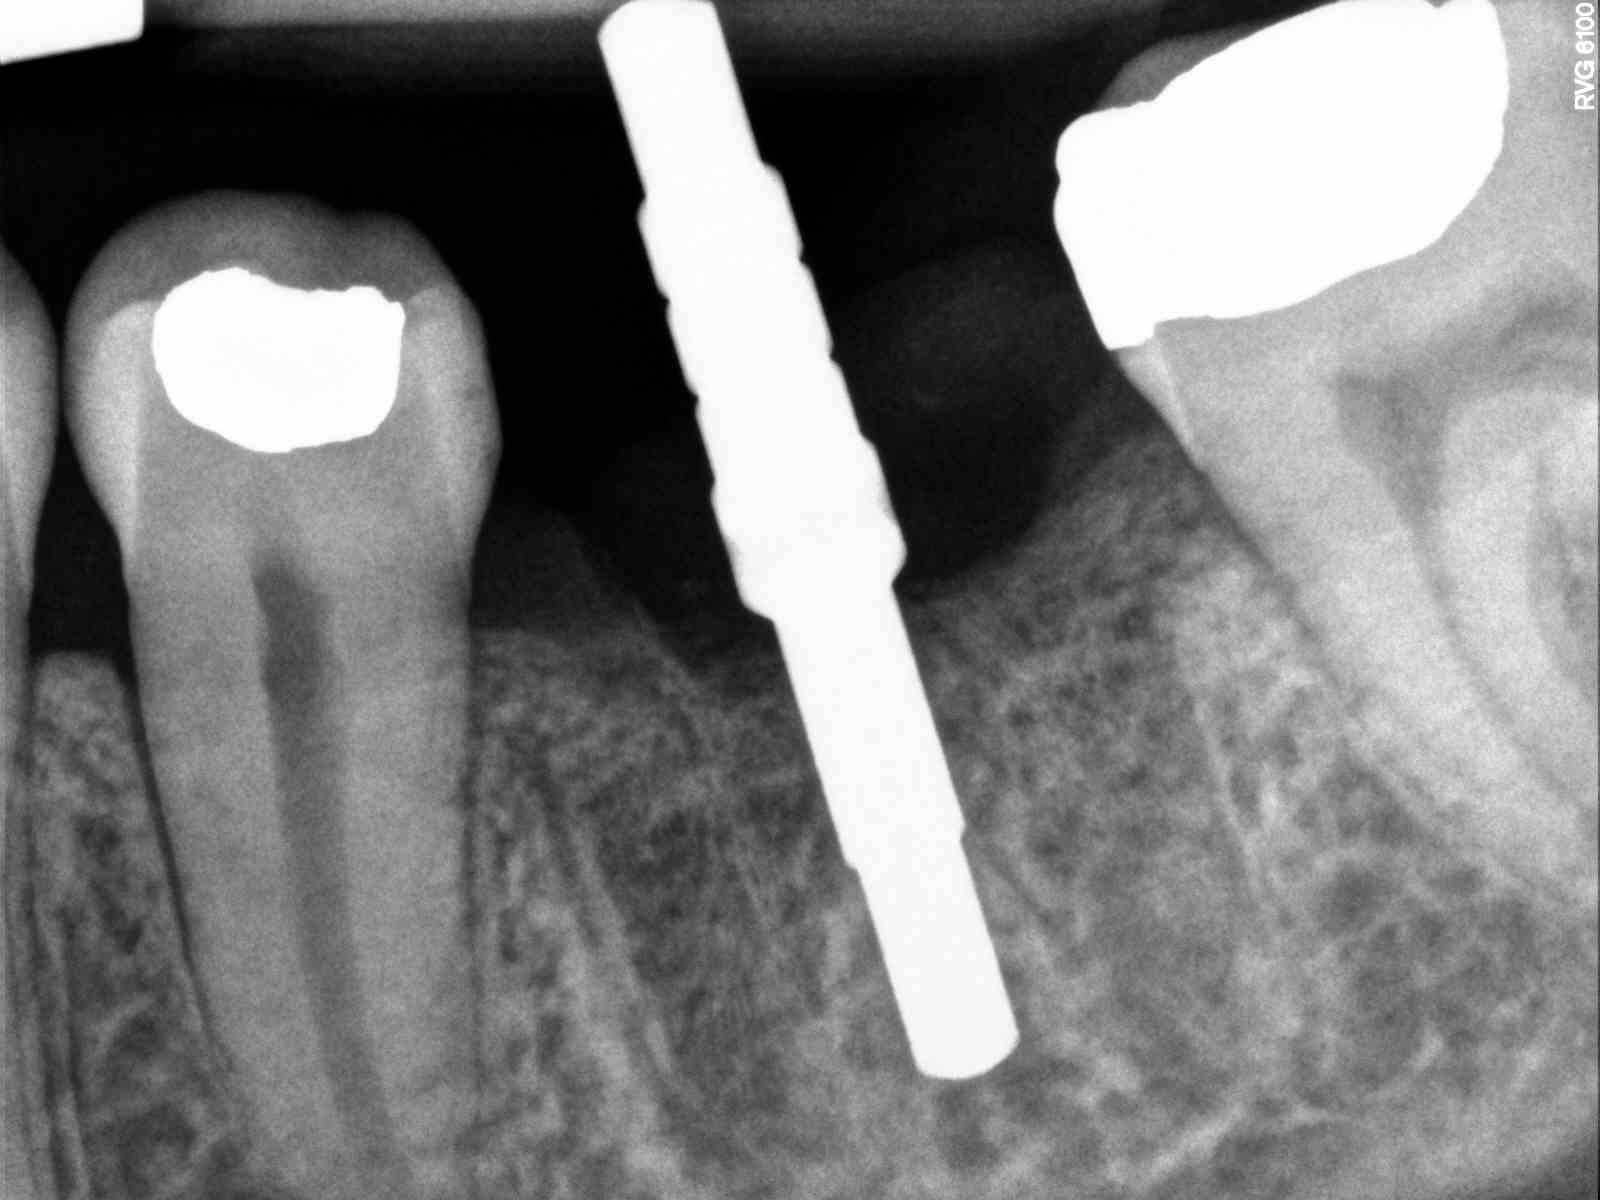

| I used Foundation for this extraction, which I don’t use anymore cause of dry socket issues, but we still had 11mm width for bone. |

| I like this one for depth more than last one. After the previous one I made the conscious effort to ensure drills down farther. |